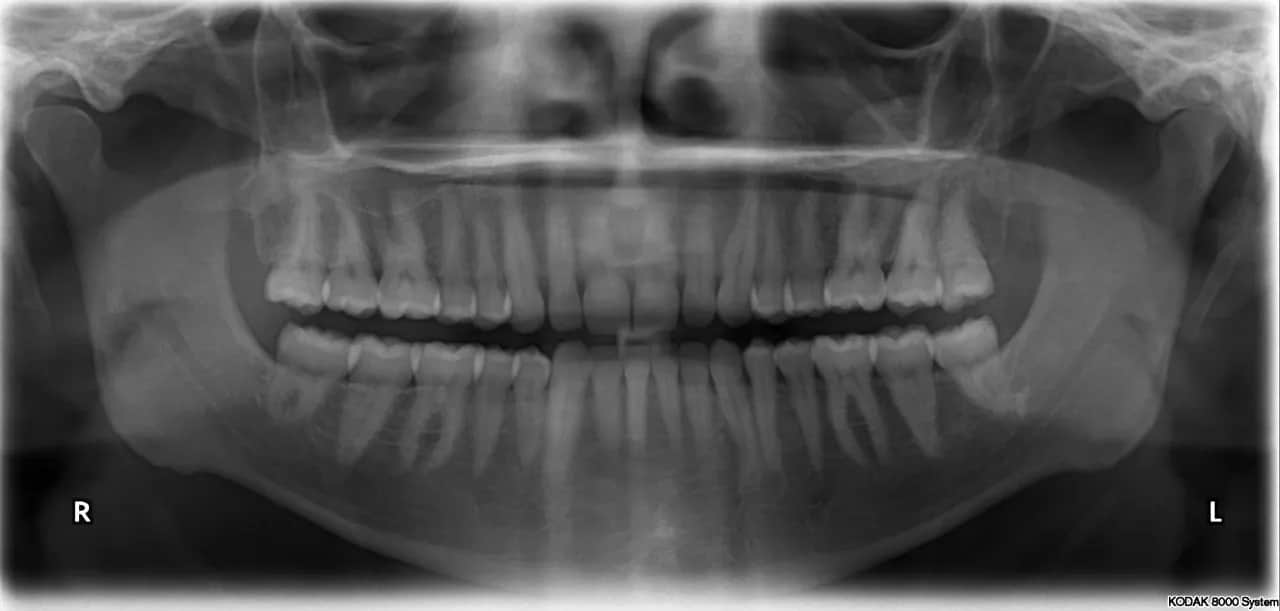

Kiedy patrzę na zdjęcie panoramiczne, widzę prawdziwą mapę jamy ustnej pacjenta. To kompleksowy obraz, na którym mogę dokładnie ocenić wiele kluczowych elementów:

- Wszystkie zęby: Zarówno te wyrżnięte, jak i te, które jeszcze czekają na swój moment, na przykład niewyrżnięte ósemki czy zęby nadliczbowe.

- Korzenie zębów: Ich kształt, długość, położenie, a także ewentualne zmiany zapalne wokół wierzchołków.

- Kości szczęki i żuchwy: Mogę ocenić ich gęstość, strukturę, a także obecność ewentualnych ubytków kostnych, na przykład w przebiegu chorób przyzębia.

- Stawy skroniowo-żuchwowe: Patrzę na ich budowę i ewentualne zmiany, które mogą być przyczyną dolegliwości bólowych czy problemów z otwieraniem ust.

- Zatoki szczękowe: Chociaż pantomogram nie jest badaniem dedykowanym do szczegółowej oceny zatok, pozwala mi na wstępne zauważenie zmian, takich jak stany zapalne czy obecność torbieli.

- Zmiany patologiczne: Mogę wykryć torbiele, guzy, a także ocenić jakość wcześniejszych wypełnień czy leczenia kanałowego.

Analiza pantomogramu to dla mnie jak czytanie otwartej księgi o zdrowiu jamy ustnej pacjenta. Na zdjęciu panoramicznym widzę nie tylko korony zębów, ale przede wszystkim ich korzenie ich długość, kształt, a także ewentualne zmiany zapalne wokół ich wierzchołków, które mogą świadczyć o martwicy miazgi lub przewlekłych infekcjach. Równie ważna jest ocena stanu kości szczęki i żuchwy. Zwracam uwagę na gęstość kości, obecność ubytków kostnych, na przykład w przebiegu zaawansowanej paradontozy, a także na wszelkie nieprawidłowości w ich strukturze. To pozwala mi ocenić ogólną kondycję podłoża dla zębów i zaplanować ewentualne zabiegi, takie jak wszczepienie implantów.

Ukryci wrogowie, których ujawnia pantomogram: próchnica, stany zapalne i torbiele

Pantomogram jest niezastąpiony w wykrywaniu "ukrytych wrogów", czyli patologii, które są niewidoczne podczas standardowego badania klinicznego. Często na zdjęciu panoramicznym ujawnia się próchnica, zwłaszcza ta międzyzębowa, która rozwija się w trudno dostępnych miejscach i jest trudna do zdiagnozowania bez RTG. Widzę również stany zapalne wokół wierzchołków korzeni, które mogą być bezobjawowe, a jednak stanowią poważne zagrożenie dla zdrowia zęba i całego organizmu. Ponadto, pantomogram pozwala na wczesne wykrycie torbieli i guzów w obrębie kości szczęki i żuchwy. Wczesne wykrycie tych zmian jest absolutnie kluczowe dla skutecznego leczenia i zapobiegania poważniejszym komplikacjom.Zęby zatrzymane i ósemki: kluczowe znaczenie pantomogramu przed usunięciem

W przypadku zębów zatrzymanych, a w szczególności ósemek, pantomogram jest dla mnie narzędziem diagnostycznym o kluczowym znaczeniu. Przed podjęciem decyzji o ekstrakcji, muszę dokładnie ocenić położenie zęba, jego orientację, głębokość, a także bliskość do ważnych struktur anatomicznych, takich jak nerw zębodołowy dolny czy zatoka szczękowa. Zdjęcie panoramiczne dostarcza mi tych wszystkich informacji, pozwalając na precyzyjne zaplanowanie zabiegu chirurgicznego. Dzięki temu mogę zminimalizować ryzyko powikłań, takich jak uszkodzenie nerwu czy otwarcie zatoki, co jest niezwykle ważne dla bezpieczeństwa pacjenta.

Chociaż pantomogram koncentruje się na uzębieniu, jego zakres obrazowania jest szerszy. Na zdjęciu panoramicznym mogę również wstępnie ocenić stawy skroniowo-żuchwowe (SSŻ). Widzę ich ogólną budowę, symetrię, a także ewentualne zmiany degeneracyjne czy nieprawidłowości w ich położeniu. Chociaż do szczegółowej diagnostyki SSŻ często potrzebne są bardziej zaawansowane badania, pantomogram daje mi cenne wskazówki. Podobnie jest z zatokami szczękowymi na zdjęciu widoczne są ich dolne części, co pozwala mi na wstępne zauważenie zmian zapalnych, pogrubienia błony śluzowej czy obecności torbieli retencyjnych. To często pierwszy sygnał, że pacjent może potrzebować konsultacji laryngologicznej.